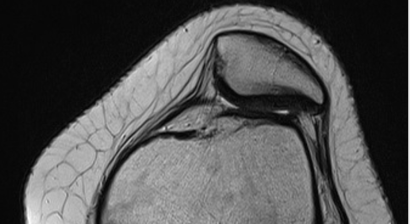

In meiner Privatordination biete ich Ihnen anhand einer ausführlichen klinischen Untersuchung sowie präziser Beurteilung der Bildgebenden Diagnostik (Röntgen, CT, MRT) eine ausführliche Erklärung Ihrer Verletzung/Diagnose die Sie verstehen!

Im Speziellen betrifft dies die Diagnose und Behandlung von akuten Verletzungen oder chronischen Schäden des Kniegelenkes. Dazu gehören insbesondere die Therapie der instabilen Kniescheibe sowie Behandlung von Bandverletzungen und Achskorrekturen bei verschiedenen Indikationen.

* Therapie der instabilen Kniescheibe (Patellaluxation), insbesondere komplexe Instabilität (Trochleadysplasie)

Therapie der instabilen Kniescheibe - Patelluxation